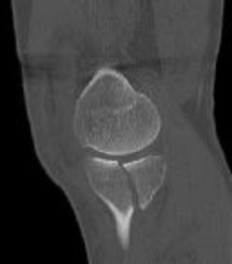

**CLINICAL SITUATION**

Figures 1 and 2 are the radiographs of a 35-year-old man who is brought into the emergency department after a motor vehicle collision. He is complaining of isolated knee pain. Examination reveals swelling, blood filled blisters, popliteal ecchymosis, joint line pain, and limited knee joint motion. His pulses and sensation are normal.

This knee injury is best described as a